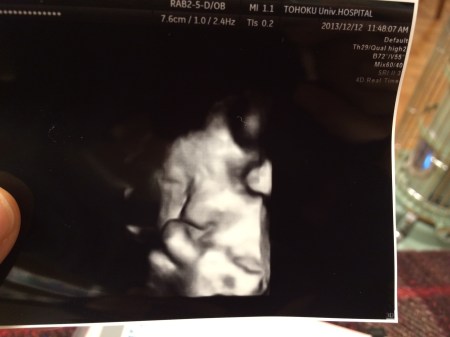

병원에서 초음파 검사할 때 마다

린짱이 너무 건강하다(쵸 겡끼~)는 이야기를 들으면

그것만으로도 우린 얼마나 행복한지!

검지손가락 빨면서 생존 본능을 보여준 린짱, 오늘 38주가 되었다.